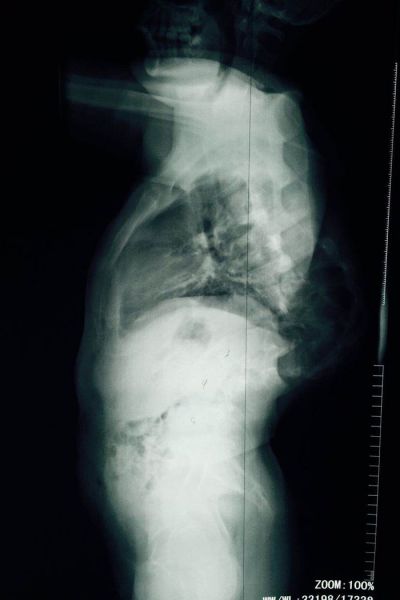

患者龙某,男,22岁,苗族,凤凰腊尔山人,未婚,精准扶贫户。自幼双肩不平,躯干倾斜20余年。入院就诊后检查发现:龙某身高146cm,双肩不等高,躯干左偏,后背剃刀背高度约12cm,胸廓畸形并与骨盆贴合,腹腔挤压明显。完善全脊柱正侧位X片、Beding相、顶点支撑相提示脊柱胸、腰段侧、后凸各约90°,椎体旋转扭成麻花型,椎体结构完全改变,相邻血管、神经也随之成角畸形。患者本人说,因为脊柱严重弯曲,除了基本生活很难自理外,疾病导致的身体畸形,走在路上所受到异样的眼光,比疾病本身更令人难过。因此他强烈要求手术,因为这是他唯一改变命运的机会……

患者于4月21日在全麻下行脊柱后路固定、截骨、矫形、植骨融合术,手术历时12个小时,过程基本顺利,完整达到手术目的。后经过一个多月的积极神经康复锻炼,患者目前基本恢复。患者妈妈激动的说:“孩子长高了,现在和我一样高了,背也直了!”。而且经过术后评估检测,患者伤口一级愈合,身高增长7cm,剃刀背高度下降8cm,双肩等高,躯干已基本平衡,脊柱畸形得到满意矫正,目前患者及家属已经满意出院。